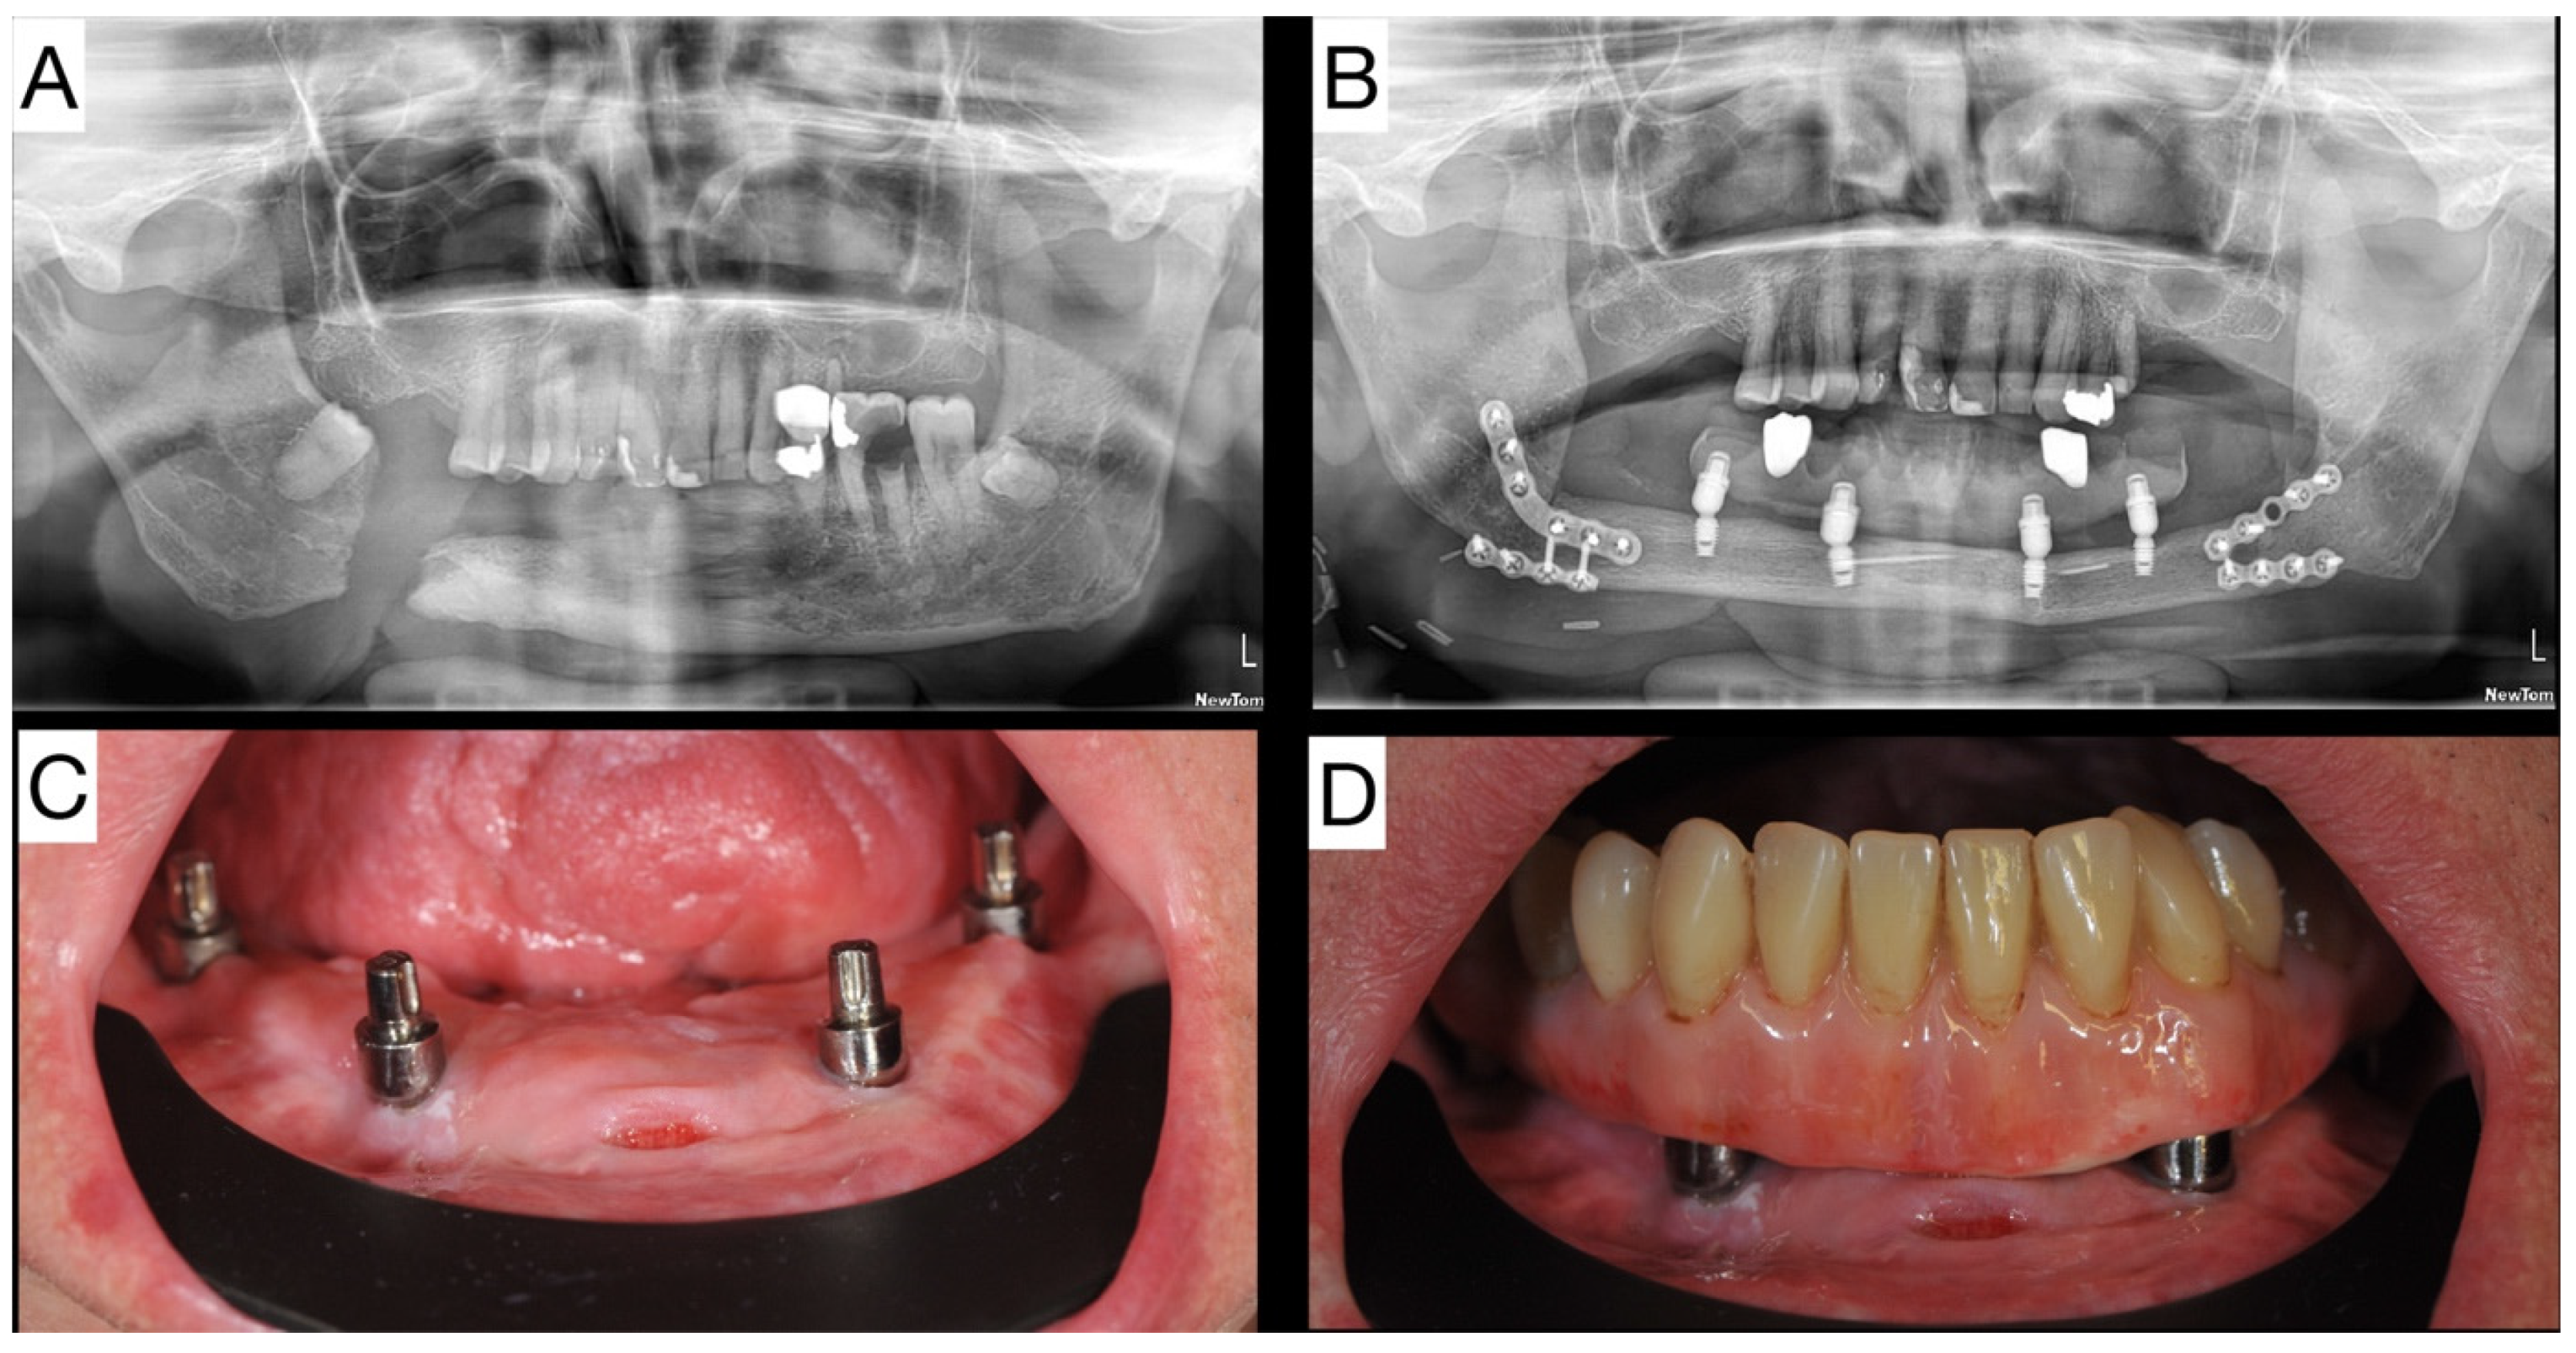

2.1. Patient 1—Case Report of Extra Short Dental Implants in Fibula Free Flap